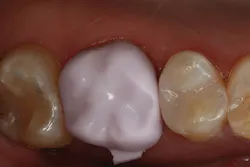

The clinical case in Figure 3 illustrates a patient who presented with a large, failing restoration containing cracks and decay. The patient was interested in an all-ceramic restoration. Occlusion was checked with articulating paper prior to treatment with a CAD/CAM restoration (figure 4). All previous restorative materials were removed from the tooth (figure 5). The tooth was restored using Grandio Core Dual Cure (Voco) build-up material (figure 6). A crown preparation was completed for a chairside CAD/CAM crown using the CEREC system (Dentsply-Sirona). The material of choice for this restoration was IPS e.max CAD (Ivoclar Vivadent), which is seen in Figure 7 after milling and in precrystallization form. The restoration was tried in and then polished, glazed, and placed in the oven for crystallization. The internal surface was then etched with 4.9% hydrofluoric acid, rinsed, and then coated with a silane coupler to create an optimal surface for bonding with the resin luting agent. The tooth was isolated and cleaned prior to etching. Once etched, the adhesive bonding agent (Futurabond U) was activated to mix the two liquids within the single-dose blister package. The blister seal was broken with the bonding agent brush and the adhesive was applied and agitated for 20 seconds. The adhesive was lightly dried for five seconds and then cured with an LED curing light for 10 seconds. A dual-cured adhesive resin luting agent (Bifix QM) was dispensed into the crown with its automix syringe (figure 8). The crown was seated and excess cement was removed after a two-second light cure. The tooth was then flossed and occlusion was checked (figure 9). The patient was very satisfied with the final result.

Figure 9: Completed restoration